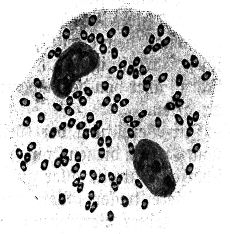

Abb. 2

Abb. 2.

Ausstrichpräparat von menschlichem Zahnschleim, gefärbt, etwa 1000fach vergrößert. Mannigfaltige Bakterien in buntem Gemisch.